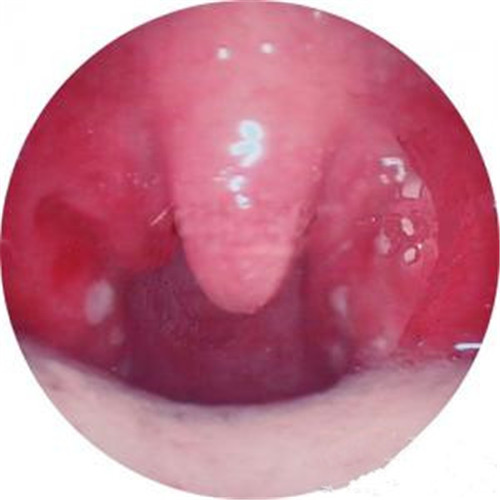

呼吸道感染口腔內部發炎